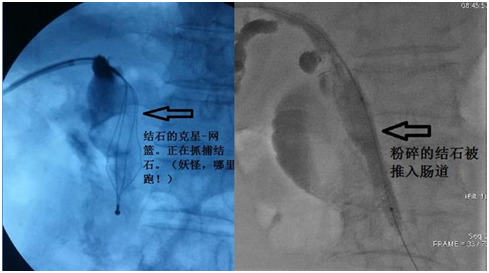

因结石比较巨大,因此治疗起来比较困难,两块结石上下重叠,给抓捕带来困难。首先先使两块石头分离,逐个将其抓捕并粉碎。其次再将粉碎的结石推入肠道,又因为患者以前做过手术,胆总管远端粘连狭窄,结石只有粉碎到足够小才能被推到肠道,又给手术增加了难度。朱亮副主任医师、王宏学主治医师联合应用多种介入技术,将结石推入肠道,术后患者恢复良好,得到了患者及家属的高度评价。